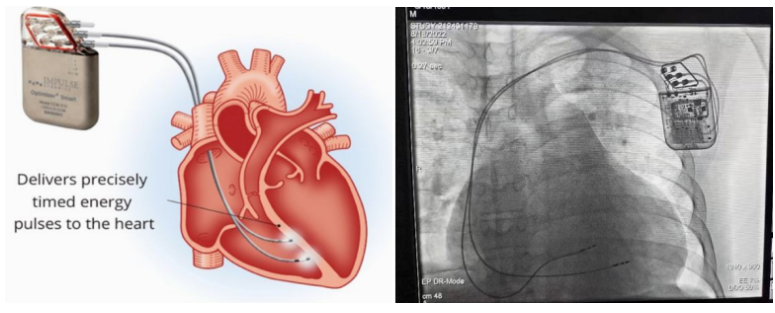

②心臟再同步治療

Cardiac Resynchronization Therapy,CRT

心臟再同步化治療,指雙心室起搏器,是通過雙心室同步起搏的方式,幫助心衰患者實現(xiàn)正常起搏的裝置。CRT包括一個口袋大小的脈沖發(fā)生器和三根電極導線,可被植入人體。通過監(jiān)測心律,在發(fā)現(xiàn)異常后,信號發(fā)生器發(fā)送電流脈沖,刺激心室重新同步,從而改善癥狀,提高患者的心臟泵血效率。目前有兩種類型的CRT裝置:植入式心臟再同步治療起搏器(CRT-P)和植入式心臟再同步治療除顫器(CRT-D)。主要區(qū)別在于后者除了改善心臟收縮同步性外,還具備除顫功能,能及時處理危及生命的室性心律失常,避免猝死。